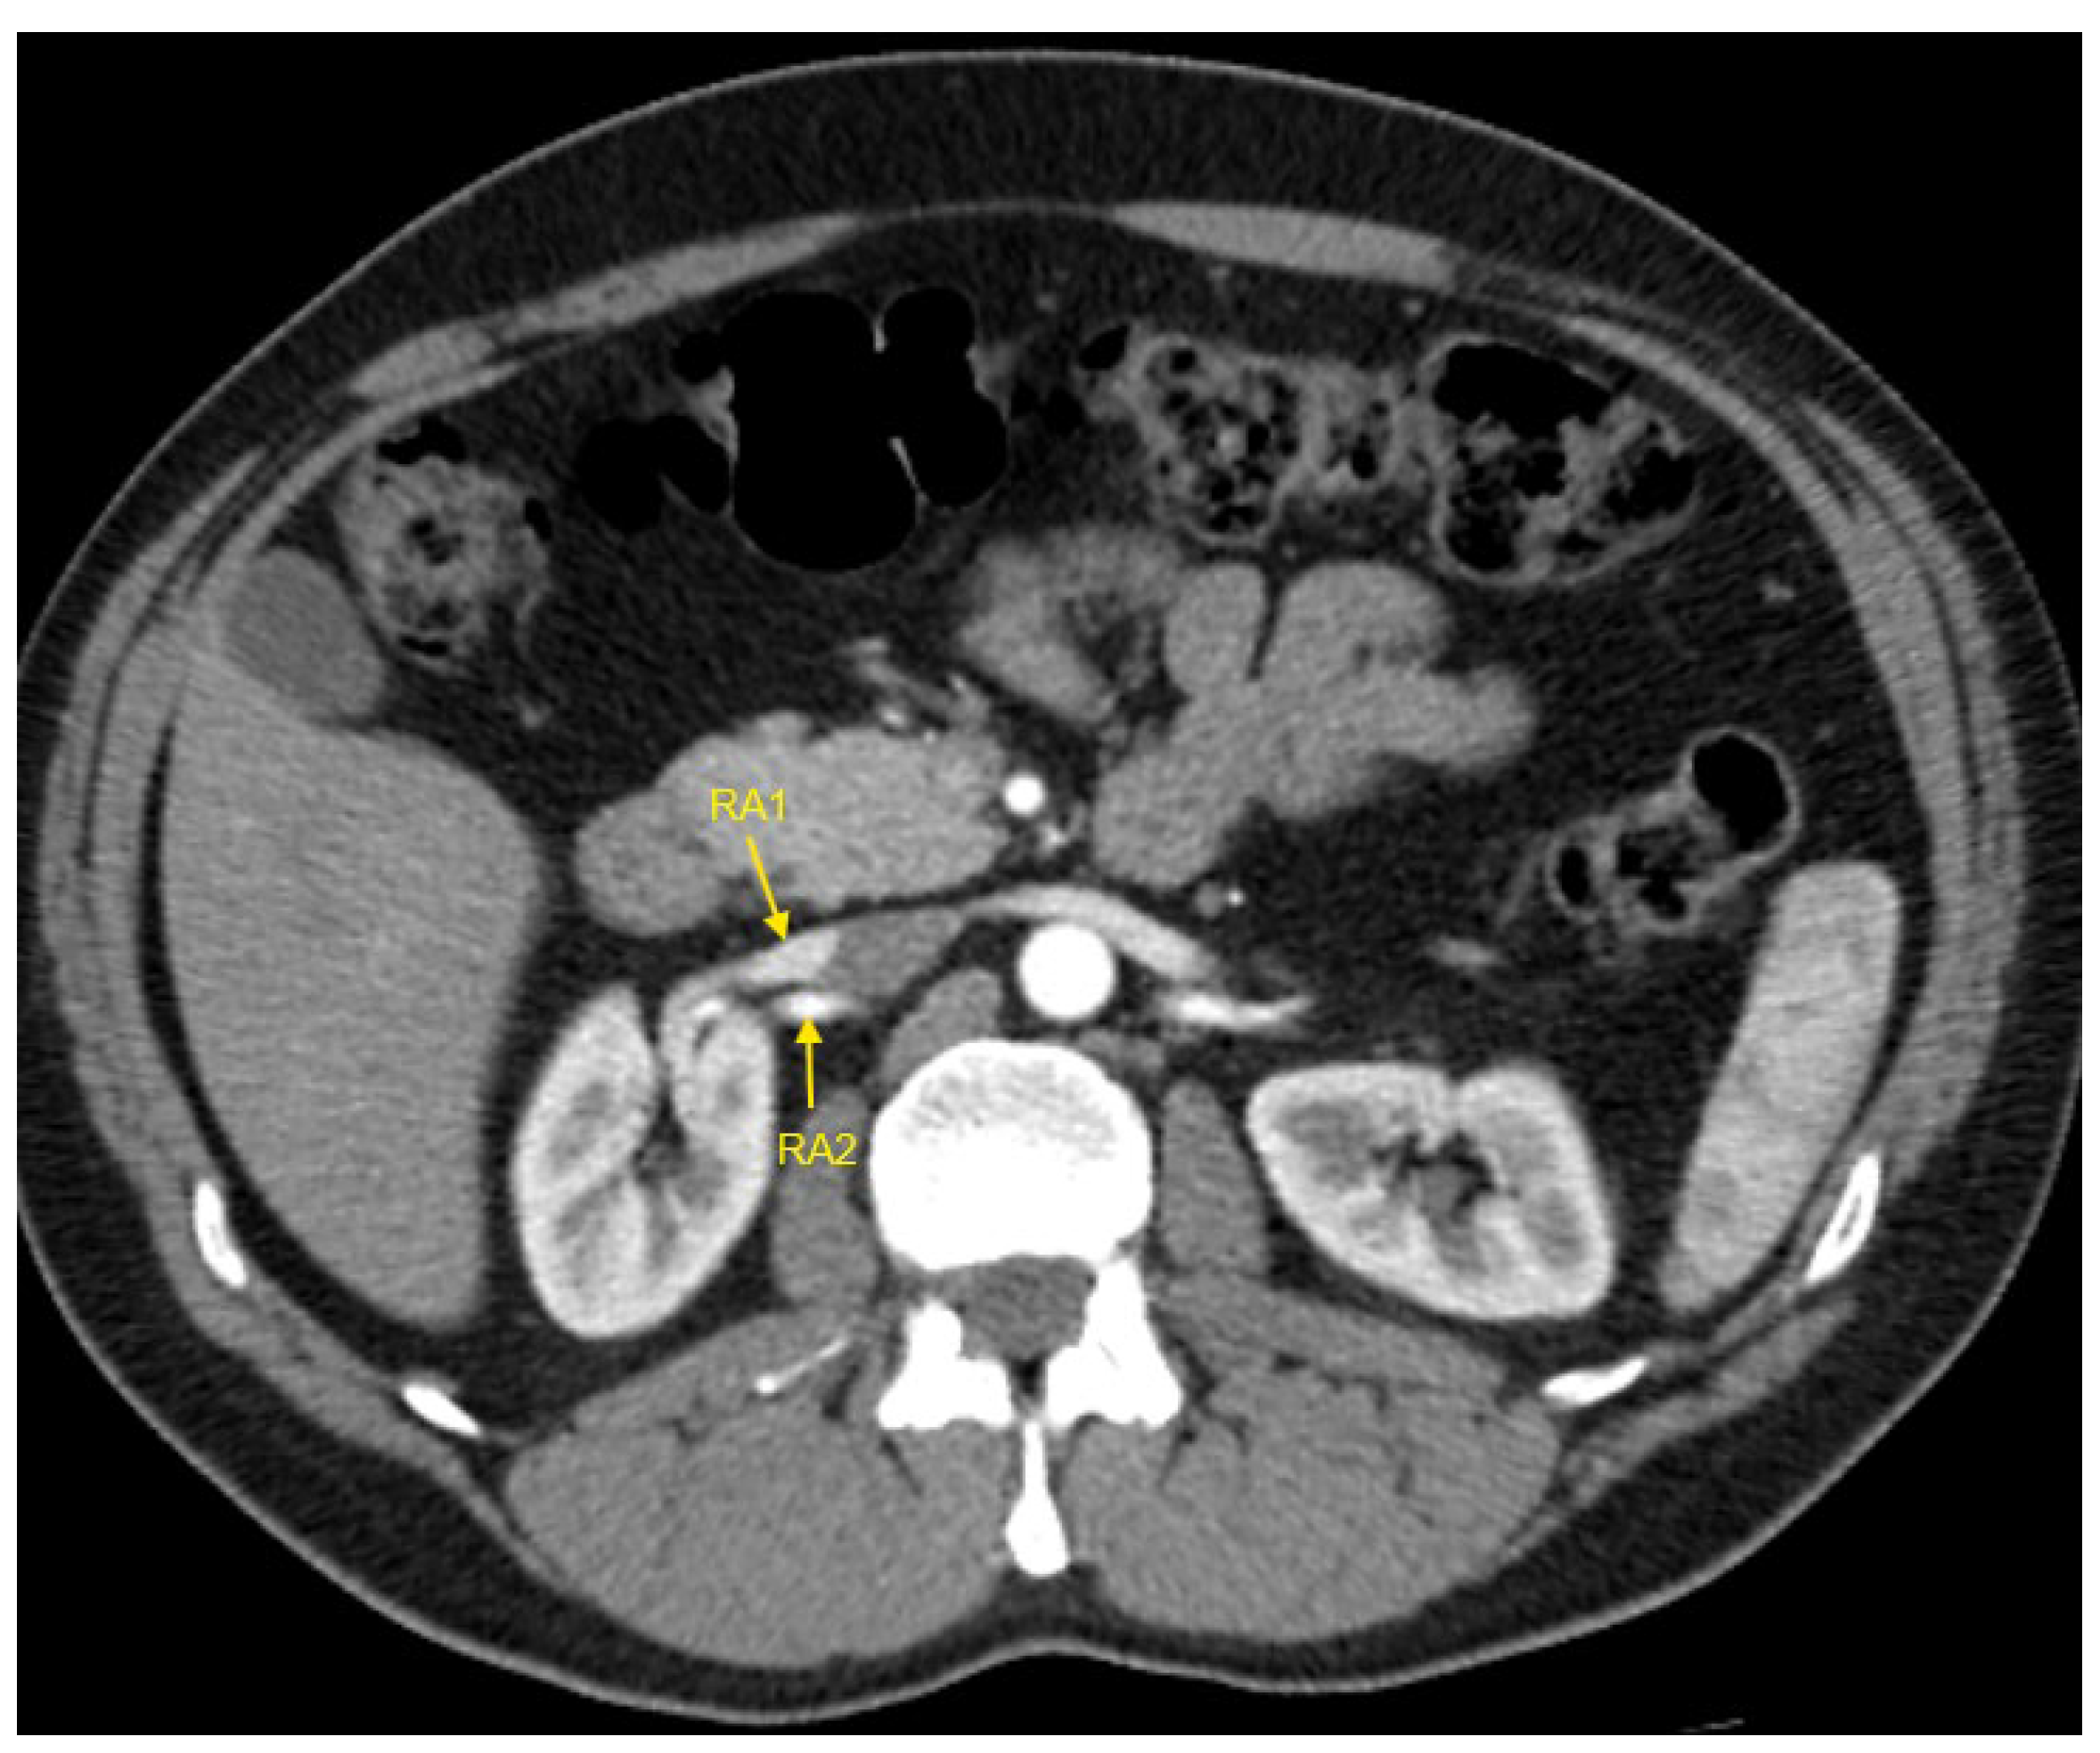

Figure 4. Contrast-enhanced CT imaging of a 43-year-old male patient with true resistant hypertension showed the presence of two renal arteries in the right kidney, indicated by the yellow arrows. CT—computed tomography; RA1—first renal artery; RA2—second renal artery.